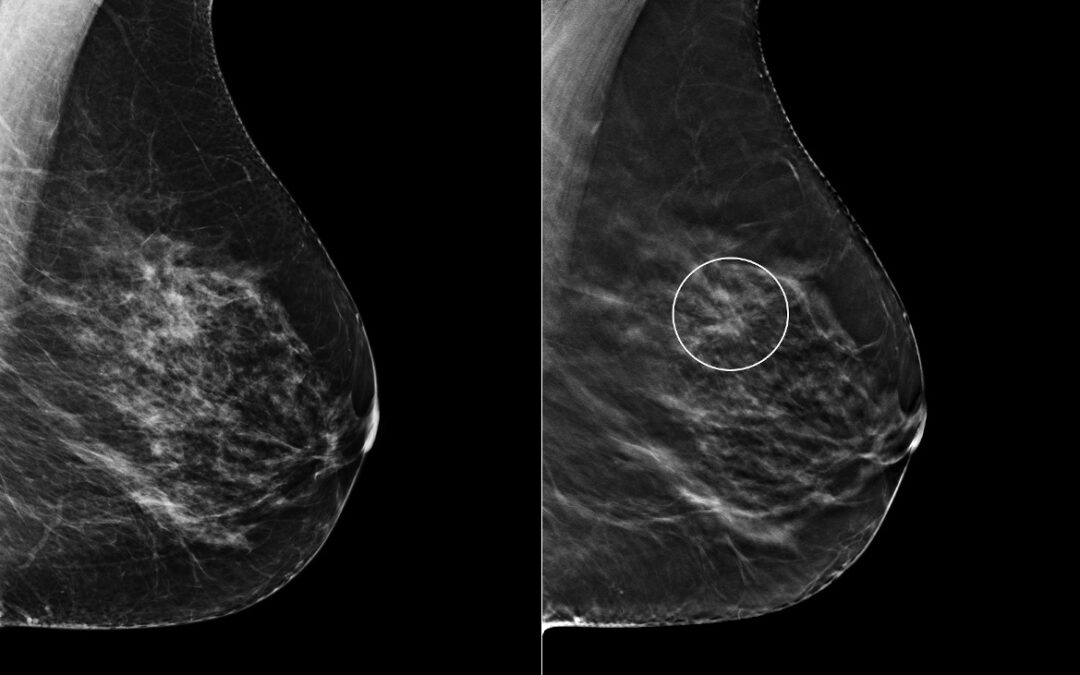

Comparing digital breast tomosynthesis (DBT) and digital mammography (DM), the authors show that DBT increases reader’s confidence and improves the inter-reader agreement.

• Digital breast tomosynthesis decreases interobserver variability in the detection of architectural distortion.

• Digital breast tomosynthesis increases reader confidence in the detection of architectural distortion.

• Digital breast tomosynthesis improves sensitivity in the detection of architectural distortion.